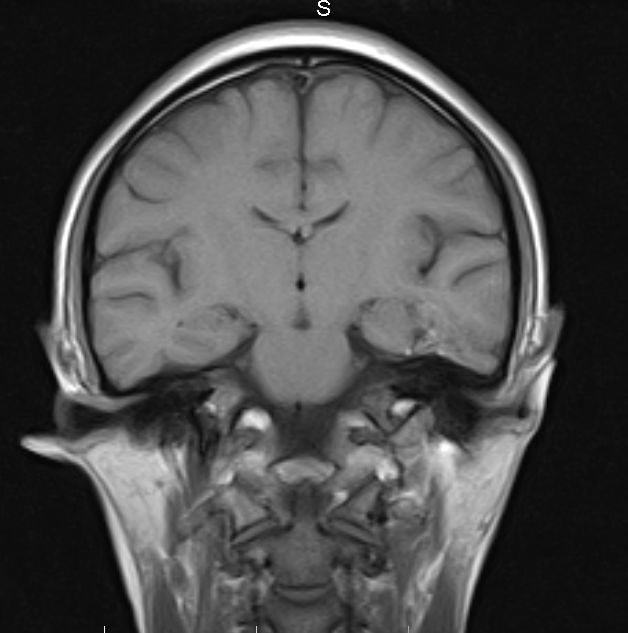

标题: MRI2379:30岁,男,癫痫10年,请各位看一下;CT示:左颞叶钙 [打印本页]

标题: MRI2379:30岁,男,癫痫10年,请各位看一下;CT示:左颞叶钙

左颞叶区见不规则点状混杂信号影

支持2楼 左颞叶区见不规则点状混杂信号影,考虑动静脉畸形。

考虑左侧颞叶脑血管畸形(avm)。----t1低等高混杂信号,t2等高信号周边较多流空血管影[冠状位明显],mra左侧大脑中动脉受压,远侧聚集.